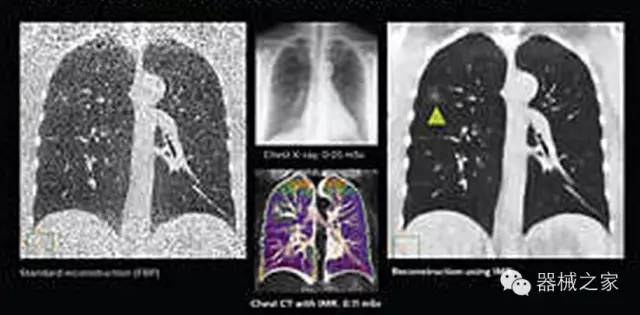

1.低劑量下的胸部顯影

IQon光譜CT能夠按照需求提供光譜量化和工具,并能通過簡單工作流程、在低劑量下對結(jié)構(gòu)進行定性分析

IQon光譜CT -- 是業(yè)界首臺以探測器為成像基礎的光譜CT,它可以在單次常規(guī)掃描下獲得傳統(tǒng)解剖影像及光譜功能影像。不僅可以提供精準的診斷信息,還可簡化工作流程、在低劑量下完成定量與定性分析。